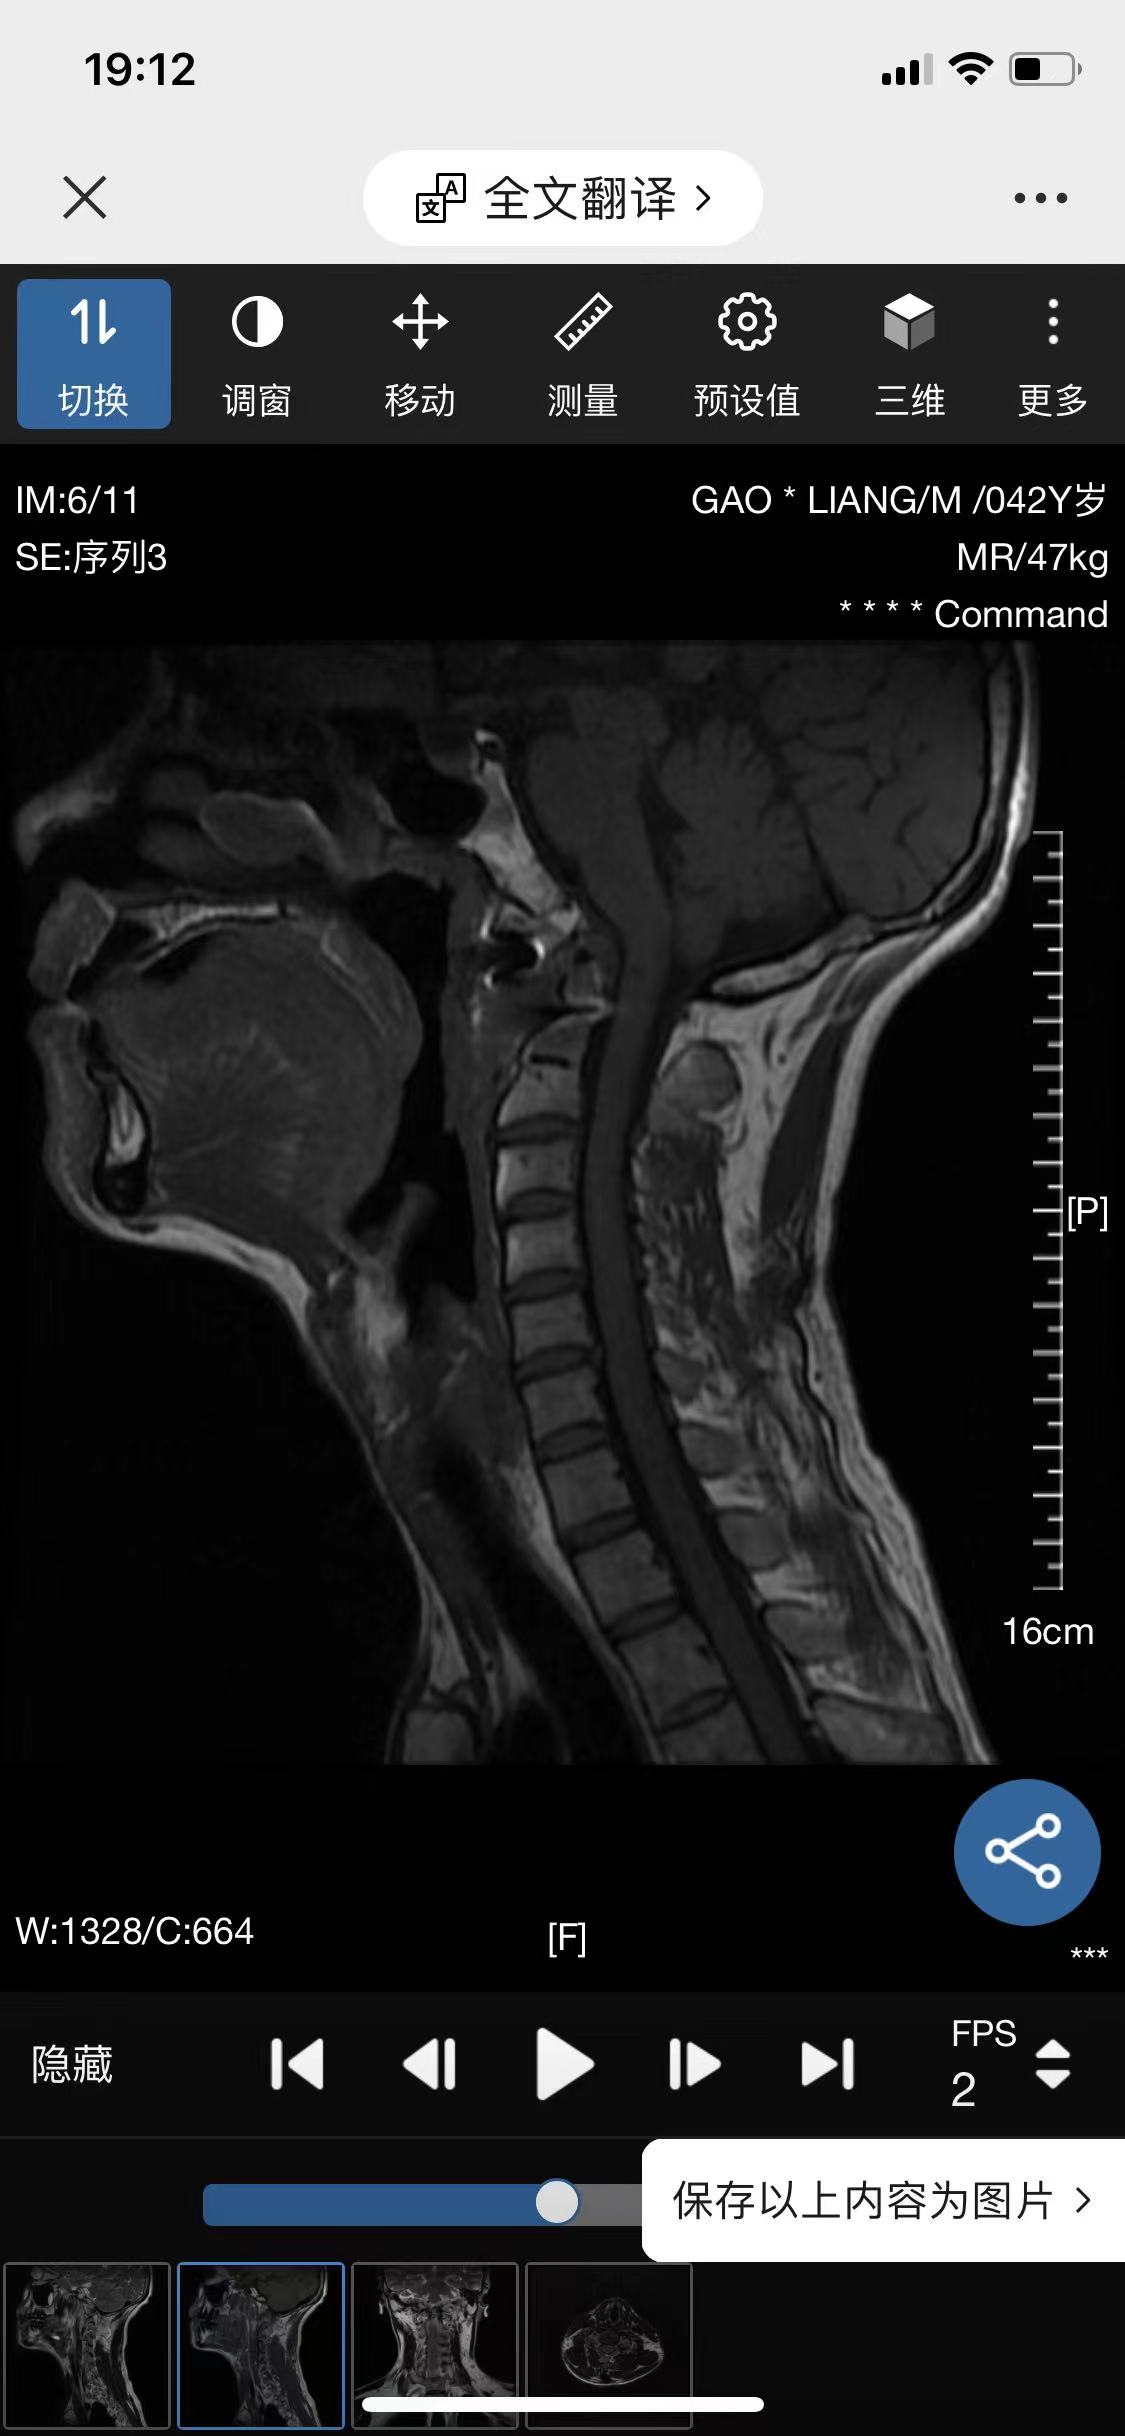

• 诊断:寰枢椎脱位

• 影像: